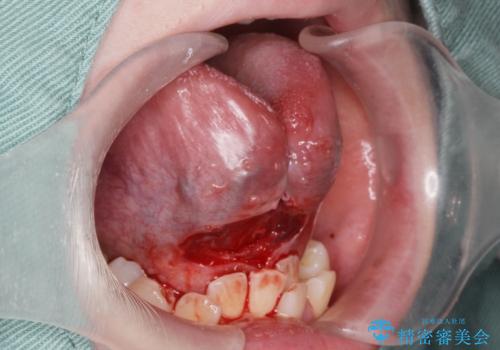

- 舌小帯を切除したいとの事で来院。

麻酔をして舌小帯切除術を行いました。

舌小帯切除は当日行うことが出来ます。

1週間後に傷口チェックと抜糸をしに来院していただきます。